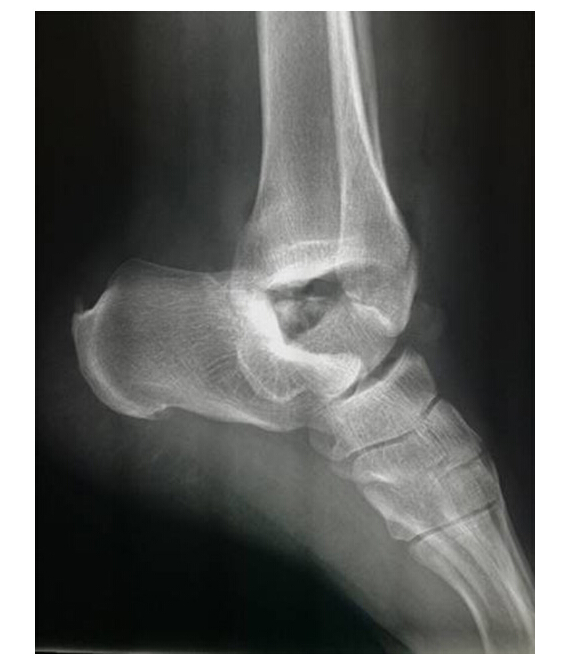

這位40多歲的患者因不幸遭遇車(chē)禍,導(dǎo)致左踝關(guān)節(jié)開(kāi)放性脫位并距骨體缺損收住醫(yī)院骨科,在急診手術(shù)時(shí),患者家屬拿來(lái)在車(chē)禍現(xiàn)場(chǎng)尋找脫出的距骨,而手術(shù)醫(yī)生見(jiàn)到的卻是家屬在車(chē)禍現(xiàn)場(chǎng)找來(lái)的石頭。

距骨是人體踝關(guān)節(jié)的一個(gè)關(guān)鍵部分,主要支持腳向各個(gè)不同的方向上移動(dòng),是連接下肢和足部的樞紐,肩負(fù)重力傳遞和運(yùn)動(dòng)的耦聯(lián),是足部重要的功能單位。距骨缺失造踝關(guān)節(jié)功能喪失造成患者的踝關(guān)節(jié)屈伸功能不變。面對(duì)距骨的缺失,傳統(tǒng)的治療方法是進(jìn)行踝關(guān)節(jié)融合術(shù),會(huì)造成踝關(guān)節(jié)不能活動(dòng),距骨置換可以實(shí)現(xiàn)踝關(guān)節(jié)和距下關(guān)節(jié)的運(yùn)動(dòng),這就使足部可以上下左右的運(yùn)動(dòng),使病人重新獲得活動(dòng)的能力。